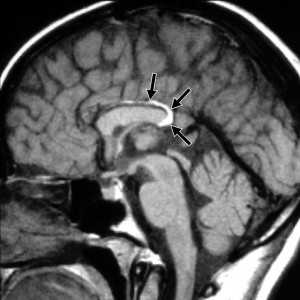

Коллоидная киста - это врождённое нейроэпителиальное образование. Коллоидная киста выстлана эпителием и имеет фиброзную капсулу. Она составляют около 1-2% объемных внутричерепных образований. Обычно диагностируются в возрасте между 30 и 50 годами. При МРТ головного мозга видно, что киста всегда расположена в переднее-верхнем отрезке III желудочка между отверстиями Монро. Контур ее четкий, форма округлая, содержимое бывает неоднородное. Размер от 3 мм до 4 см, при больших размерах она закрывает отверстия Монро и вызывает окклюзионную гидроцефалию. Сигнал зависти от примеси белка к ликвору. При наличии белкового мукоидного содержимого киста гиперинтенсивна на Т1-взвешенных МРТ и гипоинтенсивна на Т2-взвешенных МРТ, но встречаются варианты гиперинтенсивные на томограммах обоих типов кольцевидные или смешанные . Контрастирования не наблюдается.

КТ и МРТ головного мозга. Коллоидная киста III желудочка.

Коллоидная киста - это врождённое нейроэпителиальное образование. Коллоидная киста выстлана эпителием и имеет фиброзную капсулу. Она составляют около 1-2% объемных внутричерепных образований. Обычно диагностируются в возрасте между 30 и 50 годами. Всегда расположена в переднее-верхнем отрезке III желудочка между отверстиями Монро. Контур ее четкий, форма округлая, содержимое бывает неоднородное. Размер от 3 мм до 4 см, при больших размерах она закрывает отверстия Монро и вызывает окклюзионную гидроцефалию. Сигнал зависти от примеси белка к ликвору. При наличии белкового мукоидного содержимого киста гиперинтенсивна на Т1-взвешенных МРТ головного мозга и гипоинтенсивна на Т2-взвешенных МРТ, но встречаются варианты гиперинтенсивные на МРТ головного мозга обоих типов взвешенности кольцевидные или смешанные. При МРТ головного мозга с контрастированием усиления сигнала не наблюдается.